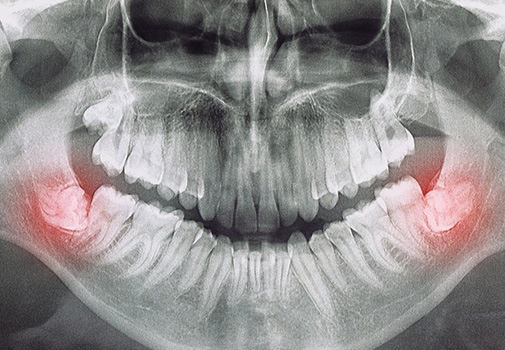

The wisdom teeth are the last set of teeth to come into the mouth, usually appearing between the ages of 16-25. However, most people don’t have enough room for them. So they become trapped within the gum and bone (impacted) or press on the nearby teeth, which can lead to pain, infection, bone loss, and other unpleasant symptoms. As a board-certified oral surgeon in Medford with significant experience removing wisdom teeth, Dr. Keyser is able to prioritize a patient’s comfort before, during, and after the procedure. If you or your teen is experiencing wisdom teeth woes, there’s no need to wait for relief—call today to schedule an appointment.

It’s a myth that everyone needs to have their wisdom teeth removed. The truth is that if they come in without issue and fit nicely, we leave them alone. However, extraction is usually recommended if a patient is experiencing the following symptoms:

There are two different approaches Dr. Keyser can take for wisdom tooth extraction based on the situation:

- Simple: If the wisdom teeth have fully erupted, then the extraction is just like it would be for any other tooth. The area is numbed, and then special instruments are used to lift and remove the tooth while causing minimal trauma to the nearby gum and bone.

Surgical: If the wisdom teeth are partially stuck in the gum and bone, or impacted, then a minor surgery is necessary. With this, any tissue that blocks access to the tooth is moved, and then the tooth is delicately extracted, often in pieces to prevent excessive force on the jaws and to preserve the surrounding anatomy such as the nerves and sinus cavity. The gums are then replaced into their customary position.